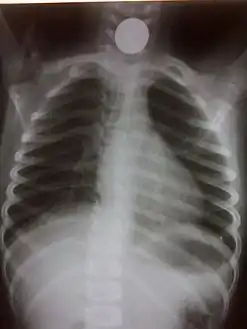

Chest radiograph showing a Venezuelan 25 cent coin lodged in the upper esophagus of a 9-year-old girl.

A coin seen on AP CXR in the esophagus